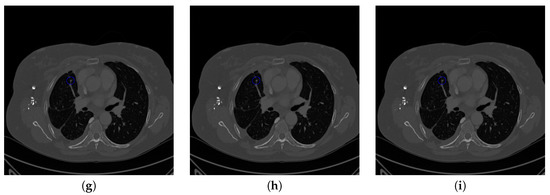

Figure 19. The result of detecting pulmonary nodules by different methods on one example image in TianChi dataset. Red circle represents the ground truth region of nodules, blue circles represent the correct estimation of pulmonary nodules, green circles represent the over-detected nodules, while yellow circles denote the nodules being omitted. (ai) are: ground truth nodule in the given chest CT image, nodule detected by 3D-FCN, MR-CNN, 3D-UNET, PRN-HSN, DCNN, CLAHE-SVM, MASK-RCNN and our proposed method.

Figure 17 and Figure 18 illustrates the performance of pulmonary nodule detection by different methods on two example images in the LUNA16 dataset. In addition, Figure 19 and Figure 20 illustrates the performance of pulmonary nodule detection by different methods on two examples images in the TianChi dataset. As marked by green circles in Figure 18b,c and Figure 19c, the 3D-FCN and MR-CNN directly detected the nodule candidates from the original CT image without pre-processing, resulting in the incorrect determination of non-nodule tissue outside lung as nodule since the outside-lung organs are not filtered out from the nodule candidates. The 3D-UNET and PRN-HSN add the lung parenchyma region segmentation stage before detecting the nodule candidates inside-lung, so they provide better performance than 3D-FCN and MR-CNN in decreasing the over-estimation rate. However, they still suffer from unsatisfactory results for the following reasons: (1) the lung parenchyma segmentation is generated by simple thresholding with morphological operations so the near-edge regions are lost, shown as the one marked by yellow circle in Figure 20d,e; (2) the convolution kernel used in nodule candidate detection of 3D-UNET is with a small receptive field to learn global features from the image, so it is likely to confuse some small tissues as true nodules with small sizes, shown as the one marked by green circle in Figure 18d and Figure 20d; and (3) the proposed hierarchical saliency network (HSN) in PRN-HSN for nodule candidate classification omits the information with different resolutions, resulting in that the small-size nodule within the weakened, low-resolution region cannot be correctly recognized, as shown by the yellow circle in Figure 18e. The DCNN method simply applies the Faster RCNN method to provide good performance with low computational cost, but it may omit the nodules on the parenchymal edge shown as yellow circles in Figure 20f. CLAHE-SVM method adds a contrast-enhancement pre-processing before the nodule detection, leads to better performance on detecting nodules in the low-contrast region. However, it is easily to over-enhance the small-size tissues and over-estimate them as nodules, as shown by the green circles in Figure 19g andFigure 20g. The detection is also implemented over the whole image, so the nodule on the parenchyma edge may be under-estimated show by the yellow circle in Figure 20g. The Mask-RCNN method provides better effects than the above methods because of the good performance of Mask-RCNN in object detection. However, the performance is not stable for the small-size tissues and the irregular-shape nodule, shown by the green circles in Figure 17h and Figure 19h, and the yellow circle in Figure 19h. The proposed method takes the advantage of a series of U-Net-like networks to perform the nodule detection following a “coarse-to-fine” order of inside-lung region detection, nodule candidate detection and nodule determination. The U-Net network is modified by embedding inception structure, replacing the convolution and pooling by dilated convolution, and adapting multi-scale pooling and multi-resolution convolution connection, for different requirements of the three stages, respectively. Moreover, it makes use of the MSE loss, VGG-19-based perceptual loss as the complement of dice loss to optimize the whole framework. Therefore, as shown in Figure 17i, Figure 18i, Figure 19i and Figure 20i, the proposed framework provides superior performance on pulmonary nodule detection with low over-estimation of non-nodule tissues at the same time.